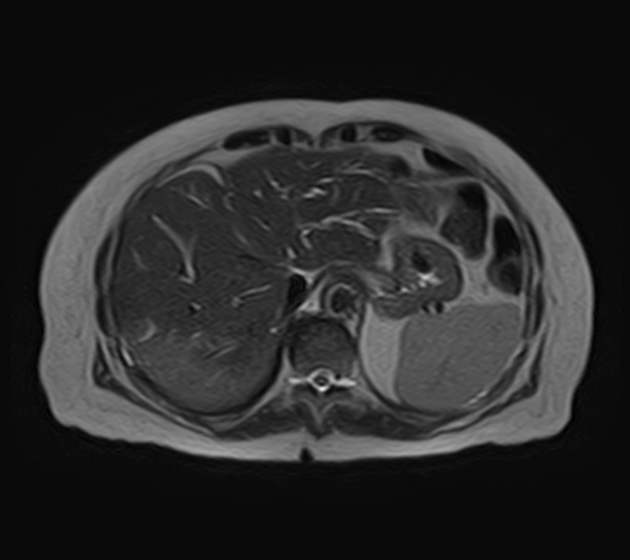

Магнитно-резонансная томография при фиброзе печени выявляет следующие анатомические признаки:

На Т1-взвешенных изображениях определяется снижение интенсивности сигнала от паренхимы печени за счёт её плотной структуры при выраженных фиброзных изменениях.

На Т2-взвешенных изображениях визуализируются гиперинтенсивные участки с неоднородной структурой, что отражает отёчные компоненты и застойные изменения на фоне портальной гипертензии.

На изображениях с подавлением сигнала от жира подчёркивается неоднородность сигнала от паренхимы и возможные фиброзные тяжи между сосудистыми структурами.

В режиме с подавлением сигнала от воды фиксируется зональность изменений в структуре печени с выраженными фиброзными перегородками и их протяжённостью.

В режиме динамического контрастного усиления определяется замедленное накопление контраста в фиброзной ткани и изменённый рисунок портального кровотока.

В режиме трёхмерной реконструкции визуализируется деформация долей печени, изменение сосудистого русла и признаки портальной гипертензии.